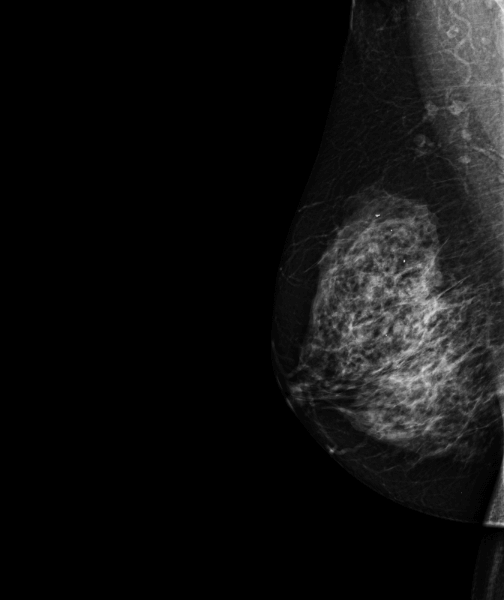

Case of the week (week 30, 2023)

69-year-old female patient, coming in for a breast cancer screening exam.

MammoScreen indicates an external right breast lesion with architectural distortion.

The ultrasound found a 10mm hypoechoic formation with irregular contours; elastography study indicates stiffness.

The biopsy performed indicates an infiltrating ductal carcinoma SBR 1, RH+, HER2-, with 5% proliferative activity. With its scoring of 5, MammoScreen successfully alerted the radiologist and facilitated the detection of the carcinoma.